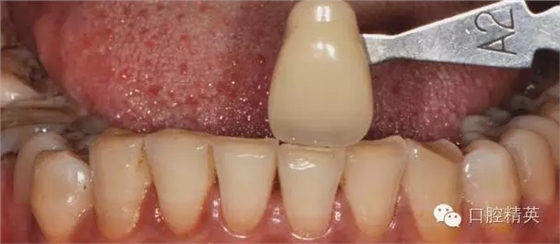

術前比色